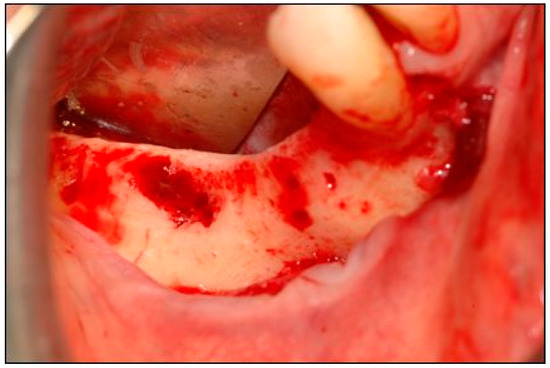

2. Case Description